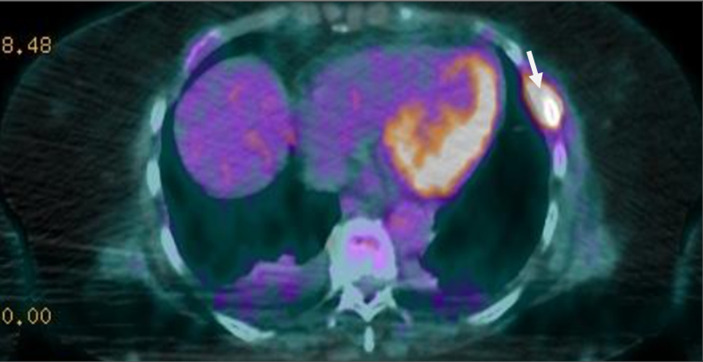

Figure 5.

image du PET scanner montrant des lésions hypermétaboliques au niveau costal en rapport avec l´ostéolyse secondaire au myélome diagnostiqué chez notre patiente